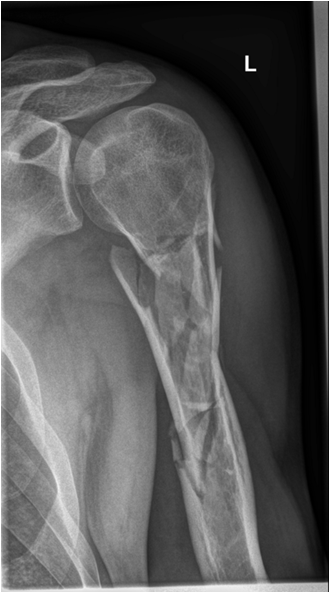

Fig. 8. Diagram showing different types of fractures: fissure or incomplete fracture, transverse simple fracture, oblique simple fracture, spiral fracture, simple and complex comminuted fracture. The x-ray example shows a severely comminuted fracture of the proximal humerus. Note that the angulation of the facture with 30-degree dorsal tilt of the distal fragment is fully seen only on the transscapular view (second plane).

Fractures may be described as displaced or in anatomical position. If they are displaced they are described in terms of position and alignment of the fragments. The distal fragment is seen in relation to the proximal fragment. In order to describe alignment the angulation or tilt of the distal fragment is assessed in relation (dorsally, volarly, inferiorly, medially, etc.) to the proximal fragment.